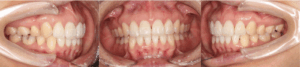

after

〈年齢・性別〉20代 女性

前歯が出ていて横顔の口元が気になるのが悩みで、思いきり笑えないことがあり相談しました。

〈診断名〉上顎前歯前突

〈装置〉インビザラインコンプリヘンシブ

〈抜歯部位〉上下顎左右4

〈治療期間〉2年6か月

〈治療費〉830,000円(税別・精密検査代込)

〈治療のリスク〉歯肉退縮、歯根吸収、歯髄壊死、痛み、治療後の後戻り